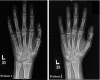

Gordon Holmes syndrome (GHS) is a distinct phenotype of autosomal recessive cerebellar ataxia, characterized by ataxia, dementia, reproductive defects and hypogonadism; it has been recently found to be associated with RNF216 mutation. We performed whole-exome sequencing and filtered the resulting novel variants by the coordinates of the shared autozygome. We identified a novel splicing variant in RNF216 that is likely to abolish the canonical splice site at the junction of exon/intron 13 (NM_207111.3:c.2061G>A). We herein report two patients with GHS caused by a novel RNF216 mutation as the first follow up report on RNF216-related GHS, and show interfamilial variability of phenotype supporting the previously reported RNF216-related cases.